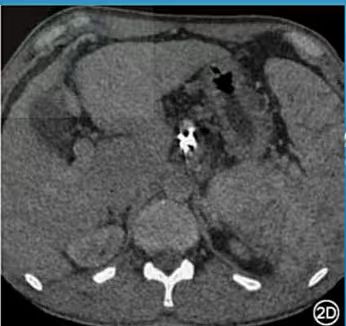

2C图示:利用单能80kev+iMAR算法组合来处理,这样既降低了金属伪影又保留了碘剂的浓度;2D图示:采用单能120kev来单独处理,发现金属伪影下降了,但是血管里的碘剂基本没有了,类似一个平扫了,这也再次佐证了随着电压的升高,增强的碘剂浓度会下降,而利用单能+迭代算法可有效地解决这一问题。